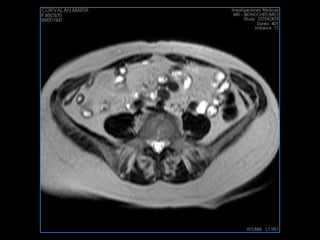

LIC ALEJANDRA GALVEZ RM DE ABDOMEN

PROTOCOLO pelvis SAG T2, Y FAT SAT (FINOS) AXIAL T1  AX FAT SAT CON   GADOLINIO :  AX T1 Y COR T1 SAT: NO  FASE: RL THK: 3MM  COIL:  GAP: (FACTOR 1.4) 1MM FOV: 40 CM NEX:2 SINCRONIZACION RESPIRATORIA EN 3 O 4 CICLOS ALE

resonancia de abdomen